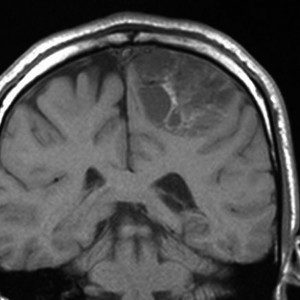

大脳皮質の毛様細胞性星細胞腫

小児期の右大脳頭頂葉にできた毛様細胞性星細胞腫です。小脳と同様に大脳にも壁在結節を作ってのう胞性増大する毛様細胞性星細胞腫というのはよくみかけます。てんかん(けいれん)発作で発症するものが多いです。腫瘍を摘出すると症候性てんかんが止まることが期待できます。治療方法は手術摘出です。腫瘍のある場所が深部で摘出術が神経脱落症状を招くと考えられる場合には,経過観察して,増大するようならガドリニウム増強される腫瘍実質部分にだけ,定位放射線治療することもあります。